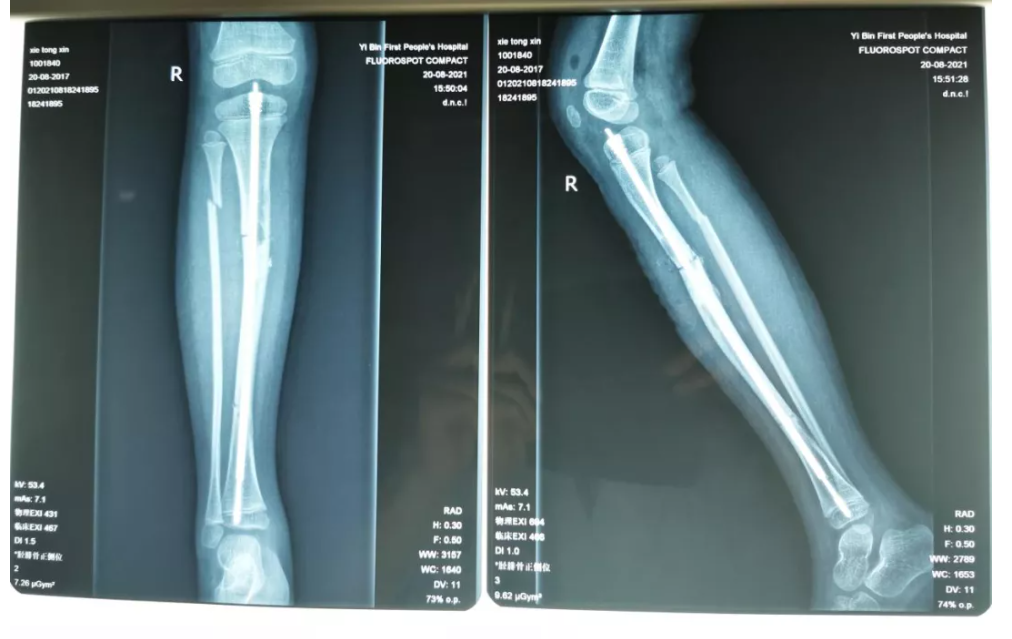

该患者因骨肿瘤引发胫骨骨折,但因为骨科矫正手术所使用的传统钢板螺钉对小孩子的创伤较大,一直在寻求其他治疗方式,家长辗转多地求医效果不佳后来到宜宾一医院骨科治疗。

“传统的钢板螺钉固定在使用后可能出现一些并发症,如再骨折,感染、骨不连等,使用可延长髓内钉可有效避免类似情况发生。”宜宾一医院骨科副主任王学文表示,经过团队成员邓学海副主任医师、郑海龙副主任医师、刘锋主任医师、黄帆博士、李冬硕士等综合分析,最后决定采用可延长髓内钉固定,既保证了骨折的良好复位,又能降低再次发生骨折的可能性。

经过前期充分准备,加上麻醉科团队协力配合,手术开展的非常顺利。

患者家长对治疗十分满意。“因为该手术创伤小,患者可以很快恢复,待骨头重新愈合后便可取出固定钉。”王学文表示,术后不久患者可完全恢复行走、运动能力。手术的成功开展标志着宜宾一医院小儿骨科取得的一大进步,未来医院将继续更好地服务广大市民朋友的生命健康。(宜宾市第一人民医院供稿)